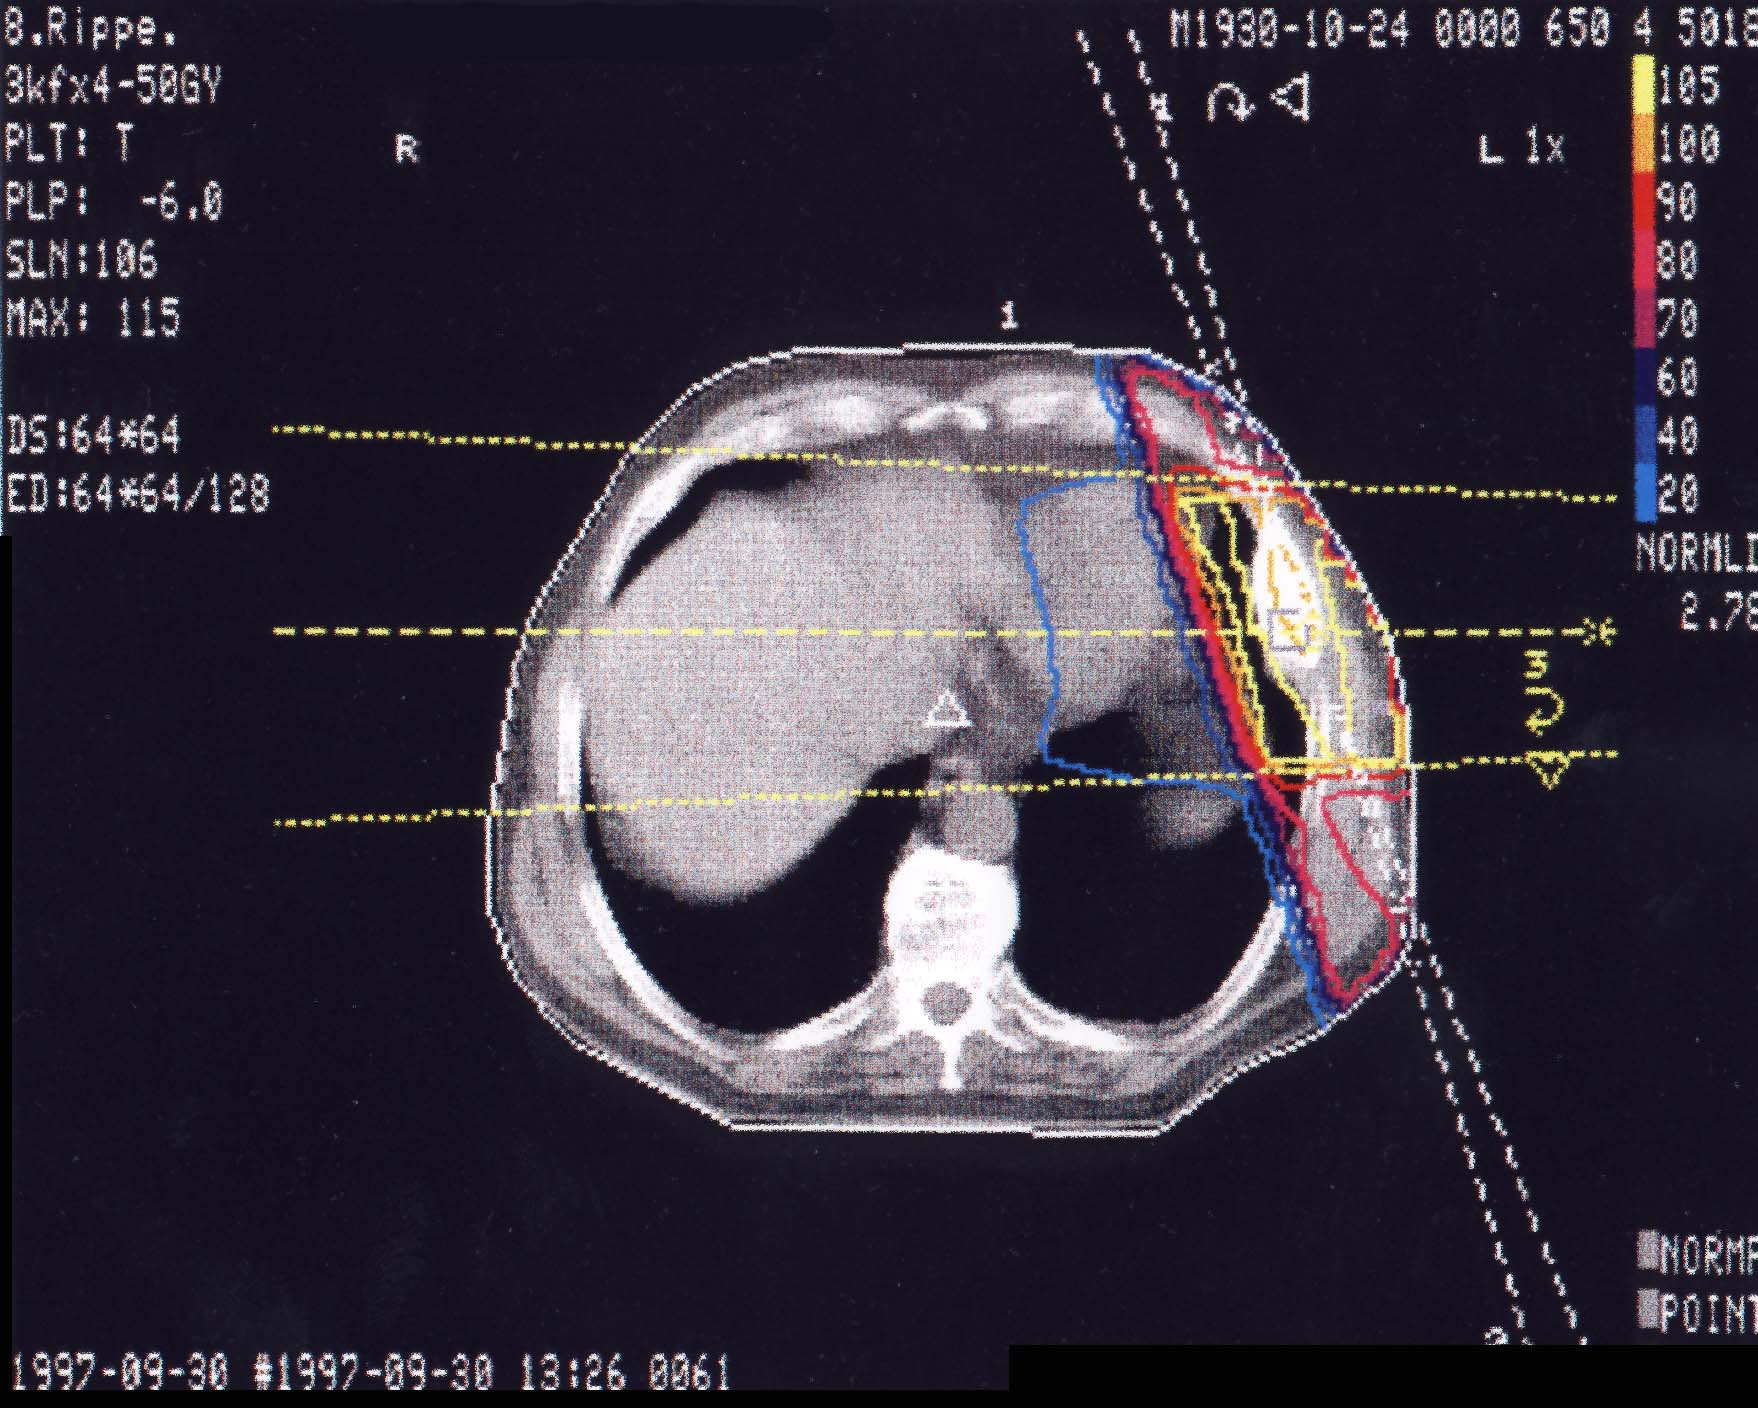

Tumore des Knochens: Bestrahlungsplan

Einführung aktuelle Bilder - Einführung Bestrahlungspläne - Einführung Demonstration